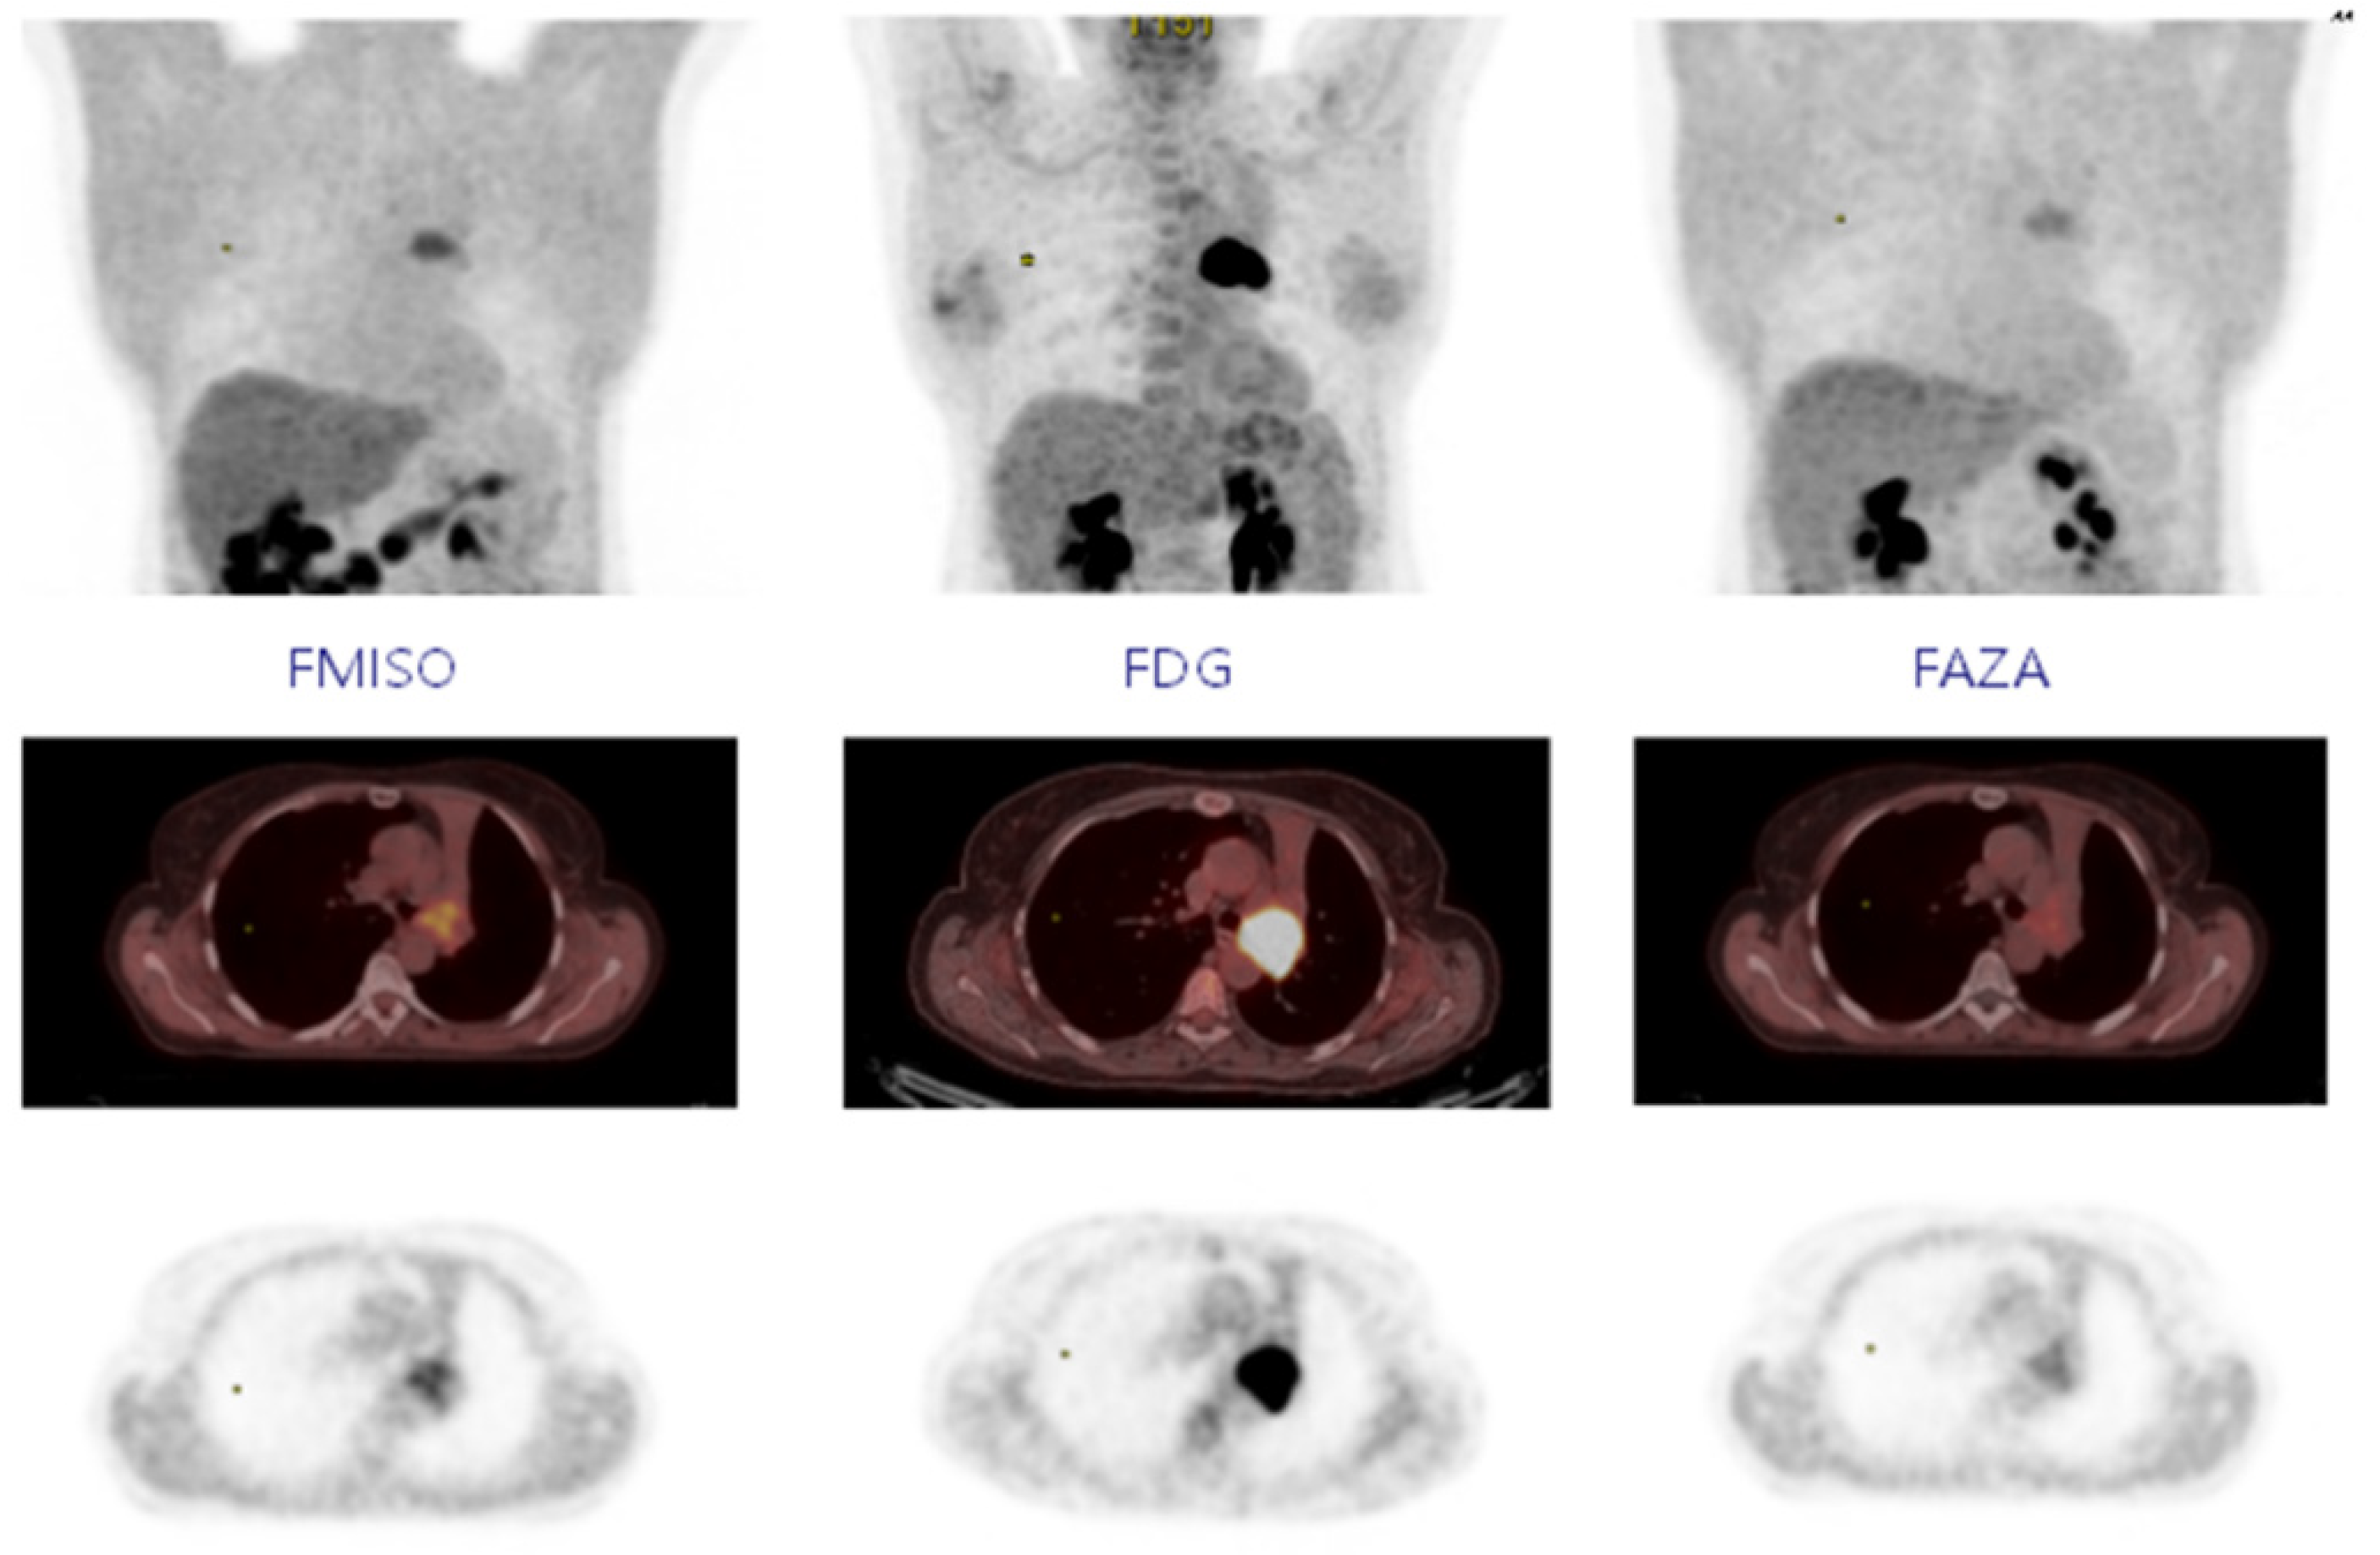

- Thureau, S.; Piton, N.; Gouel, P.; Modzelewski, R.; Dujon, A.; Baste, J.M.; Melki, J.; Rinieri, P.; Peillon, C.; Rastelli, O.; et al. First comparison between [18F]-FMISO and [18F]-Faza for preoperative pet imaging of hypoxia in lung cancer. Cancers 2021, 13, 4101. [Google Scholar] [CrossRef]